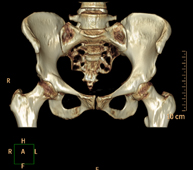

- Pelvic bone CT

Radiological examination based on an X-ray system and detectors that rotate around the patient, reconstructing the images by computer (multidetector computed tomography - MDCT) to study the bones, muscles and joints of the pelvis.

- Hip CT

Radiological examination based on an X-ray system and detectors that rotate around the patient, reconstructing the images by computer (multidetector computed tomography - MDCT) to study the bones, muscles and joints of the hips.